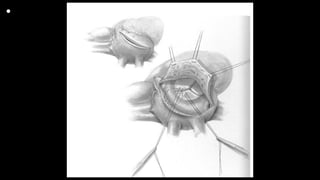

FIGURE 1. The drawing shows the various types of PV

plasty procedures

that can be performed in addition to PV balloon dilation:

(A) dysplastic PV with commissure fusion (effective PV

opening); (B) PV commissurotomy (true initial PV

annulus diameter); (C) PV balloon dilation and (D) final

PV annulus diameter; (E) simple additional PV plasty

(including PV leaflet repair and resuspension); (F-G)

complex additional PV plasty, including PV leaflet

delamination (F) and patch augmentation when needed

and resuspension (G).

FIGURE E1. A-D, An excised bovine heart model was used to better

understand the delamination plasty technique that was used to

extend the PV cusp coaptation area, especially in patients with a

hypoplastic PV annulus. In this model, the normal PV was exposed

and examined through a longitudinal incision in the pulmonary

trunk. After excision of 1 cusp of the tricuspid PV (creating a gap in

coaptation mimicking the gap after PV balloon dilation in patients

with a very hypoplastic PV annulus), a delamination plasty was

performed on the other 2 cusps, thus extending their coaptation

surface. Both cusps were then extended with triangles of biological

tissue substitute and resuspended from the sinotubular junction,

resulting in complete coverage of the PV annular area, simulating a

bicuspid PV. A, Normal tricuspid PV; (B) removal of 1 PV cusp; (C) PV

cusp delamination and leaflet extension, and (D) functionally

bicuspid PV.